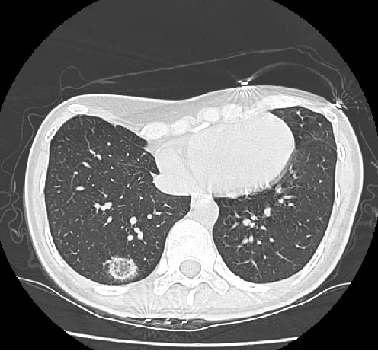

斑片状肺泡浸润影(典型COP

孤立性阴影(局灶性COP

浸润性阴影(浸润性COP

1、反晕轮征

2、进行性肺纤维化并网格及实变

3、多发性结节

4、支气管中央型实变

5、不规则线或带

6、小叶周围型阴影

多灶性实变影

孤立性病灶

支气管中央型

结节型

纤维化型

反晕轮征reverse halo